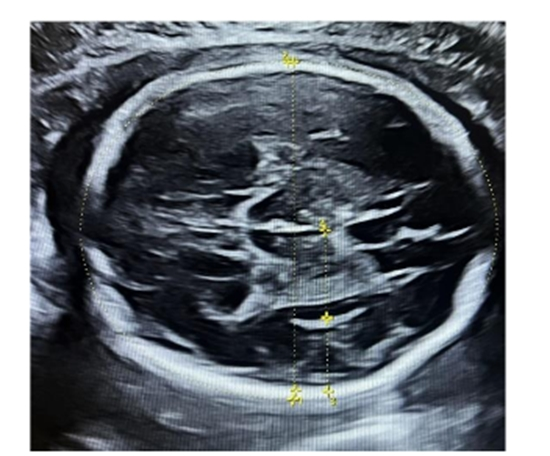

Background: Cortical folding during fetal brain development reflects neural matur- ation. Fetal growth restriction (FGR) may disrupt this process, potentially affecting neurodevelopmental outcomes. Although ultrasound enables noninvasive sulcal assessment, so normative data and objective tools are lacking. The purpose of the current study was to assess the impact of FGR on fetal cortical development using neurosonography and establish a third-trimester nomogram for cortical maturation. Methods: This prospective study included 425 singleton pregnancies (330 appropri- ate-for-gestational-age [AGA], 54 symmetrical FGR, and 41 asymmetrical FGR) at 28–36 weeks. Conducted at a Tehran tertiary center (2023–2024), the study included cases with normal anatomy and negative aneuploidy screening. Neurosonographic parameters including Sylvian fissure (SF), insula, parieto-occipital fissure (POF), cavum septum pellucidum (CSP) width, and ventricular diameter were measured and the ratios calculated relative to biparietal diameter (BPD). ANOVA and post-hoc tests were applied and statistical significance was set at p<0.05. Results: No significant differences in neurosonographic ratios (e.g., SF/Insula, POF/ BPD, CSPW/BPD) were found between AGA and FGR groups. However, unadjust- ed SF and insular depths were reduced in symmetrical FGR fetuses with head cir- cumference (HC) <10th percentile. Asymmetrical FGR showed no differences. A gestational-age-based nomogram was developed for AGA fetuses. Conclusion: While absolute sulcal measurements vary with head size in FGR, biometric adjustments (e.g., BPD ratios) improve cortical maturation assessment. The study supports ratio-based neurosonography and provides normative data for objective fetal brain evaluation